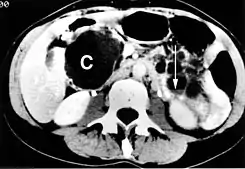

Quiste del páncreas

Un gran quiste pancreático en el proceso unciforme del páncreas